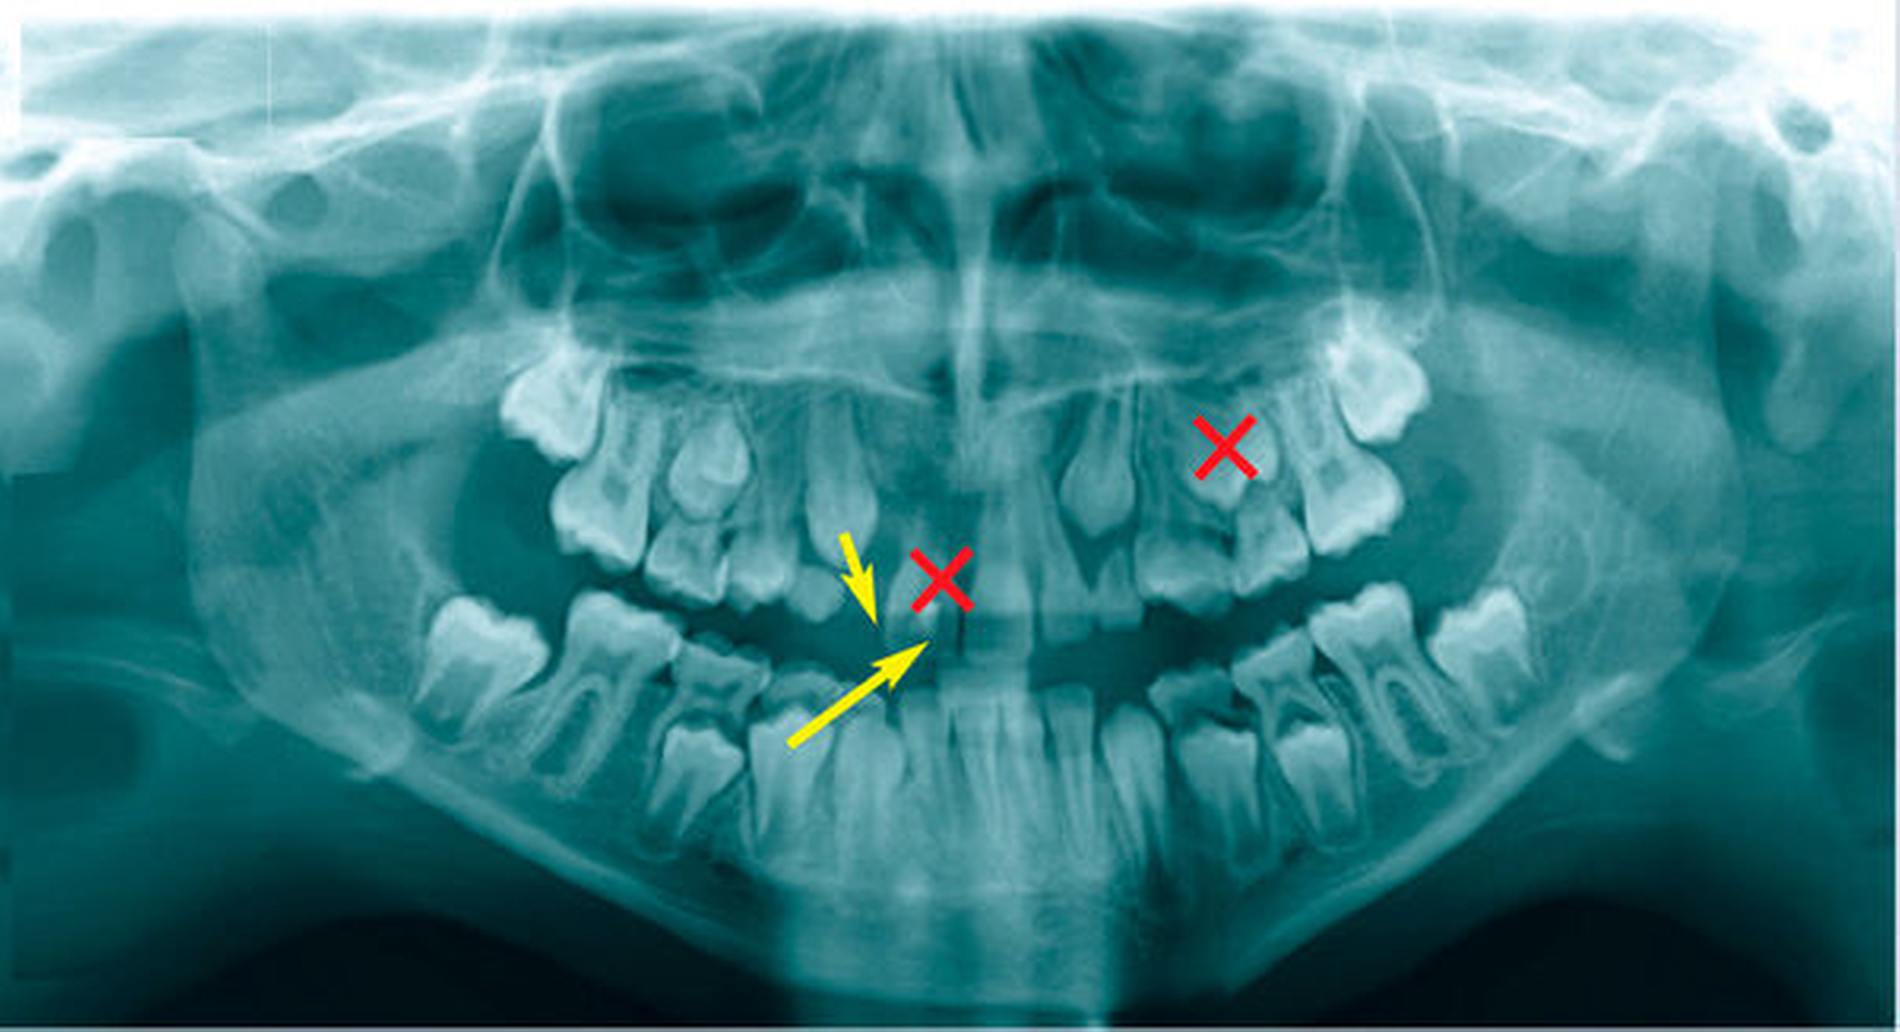

In der Regel sollte bei einem Frontzahnverlust im Oberkiefer ein Prämolar mit einer Wurzel verwendet werden. Die Wurzel einwurzeliger Prämolaren und deren Form sind in einer Schneidezahnalveole passfähiger und geeigneter für die parodontale Regeneration als ein Prämolar mit zwei Wurzeln. Der Prämolar sollte nach Möglichkeit aus dem Unterkiefer entnommen werden, da bei einem Misserfolg zwei Zähne innerhalb eines Kiefers fehlen würden. In der Regel wird die Extraktionslücke kieferorthopädisch mittels skelettaler Verankerung geschlossen. Zuvor ist die Anlage des dritten Molaren im betreffenden Quadranten zu prüfen, der nach kieferorthopädischer Einstellung mit dem zweiten Molaren des Oberkiefers okkludiert.

Das Wurzelwachstum des Transplantats sollte zum Zeitpunkt der Entnahme nicht mehr als zwei Drittel betragen. Dies kann eine operative Freilegung notwendig machen (Abb. 3).